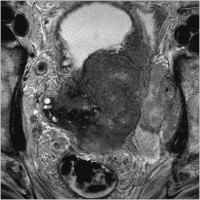

Palliative radikale (Zysto-) Prostatektomie bei lokal fortgeschrittenem kastrationsresistentem Prostatakarzinom (KRPCA)

Journal für Urologie und Urogynäkologie 2011; 18 (2) (Ausgabe für Österreich): 14-16 Journal für Urologie und Urogynäkologie 2011; 18 (2) (Ausgabe für Schweiz): 14-16 Volltext (PDF) Summary Praxisrelevanz Abbildungen